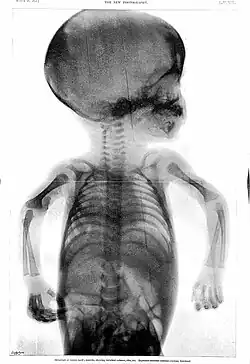

Rowland's career began in medical journalism while he was still a medical student when, in 1896, as Hart's intern, the year following the discovery of X-rays,[6] the BMJ appointed Rowland as "Special Commissioner" to produce a report on the clinical use of X-rays titled "Report on the Application of the New Photography in Medicine and Surgery."[3][6][a] It was published in 17 parts between 8 February 1896 and 12 June 1897.[3] In May 1896, he founded the world's first X-ray journal, the Archives of Clinical Skiagraph, a radiology journal that preceded the British Journal of Radiology.[3][6] In the preface to the first issue, written in April 1896, he wrote that "the object of this publication is to put on record in permanent form some sort of the most striking applications of the new photography to the needs of medicine and surgery".[6] He coined the term "skiagraphy" to describe the making of X-ray pictures and wrote some of the early works on radiology.[3] Without any radiology experts or X-ray departments at the time, his journal became an essential reading.[6]